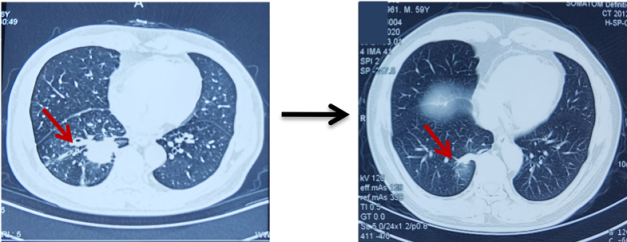

骨骼是肺癌常见的转移部位之一,骨转移癌会导致骨痛、病理性骨折、脊髓压迫、高钙血症等骨相关事件(SRE),其中,骨痛是骨转移癌最常见的临床症状,严重影响患者生活质量。地舒单抗,首个落户中国的核因子κB受体活化因子配体(RANKL)抑制剂,为防治SRE提供新的选择。本次分享地舒单抗治疗以骨痛为主要症状的EGFR突变晚期肺癌骨转移患者案例,希望为SRE的防治带来启迪与思考。 白引苗 空军军医大学第一附属医院肿瘤科 主治医师 中国抗癌协会肿瘤标志物专业委员会 委员 陕西省抗癌协会肿瘤化疗专业委员会 委员 陕西省抗癌协会肿瘤热疗专业委员会 委员 陕西省抗癌协会多原发和不明原发肿瘤专业委员会委员 擅长食管癌、胃癌、结直肠癌、胰腺癌等消化系统、肺癌及妇科常见恶性肿瘤的化疗、靶向治疗及免疫治疗等内科治疗。参译著作1部,参编著作1部,发表核心期刊论文多篇。 一般资料:患者男性,60岁 主诉:右侧肩部疼痛 现病史:2019年8月因右侧肩部疼痛于外院就诊,疼痛NRS评分3-4分,口服依托考昔症状可缓解 个人史:否认吸烟、饮酒嗜好 家族史:1兄因“胃癌”病故 辅助检查: 外院右肱骨MRI:右侧肱骨骨转移可能,合并肱骨中段骨质破坏。 外院胸部CT(图1):右肺下叶周围型肺癌,可疑肺门、纵隔淋巴结转移,T3/4/8椎体骨转移。 图1 胸部CT(箭头指示右肺下叶病变) PET/CT(18F-FDG)(图2-3):右肺下叶基底段软组织病变(3.7 cm×4.6 cm×4.7 cm,SUV max 6.9,平均值6),浅分叶、边缘见毛刺;右侧锁骨上下区、隆突区稍大淋巴结(长径0.6 cm-1.4 cm,SUV max 2.5-4.6,平均值2.2-3.2),考虑转移;脊柱多个椎体及附件、双侧多个肋骨、骨盆多处、双侧股骨上段多发骨质破坏(SUV max 2.0-5.7,平均值1.7-3.9),考虑转移。 图2 PET/CT提示右肺下叶基底段病变及右锁骨上下区、隆突区稍大淋巴结 图3 PET/CT提示多发骨质破坏 患者接受CT引导下经皮右肺病变穿刺活检,病理(图4):光镜见异型细胞呈条索状、腺管样排列,细胞核大、深染,异型性明显;免疫组化:AE1/AE3(+),CK5/6(-),CK7(+),CK8/18(+),P40(-),P63(-), Napsin A(+),ALK(D5F3 Ventana IHC)(-),TTF-1(+),Ki67 30%,支持腺癌。 肿瘤标志物:CYFRA21-1 5.8 ng/ml(参考值:0-3.3 ng/ml),CEA、SCC、NSE正常。 基因检测:EGFR基因19del突变。KRAS、NRAS、PIK3CA、BRAF、HER-2基因未检测到突变;ALK、ROS1、RET基因未检测到融合。 诊断:肺恶性肿瘤(右侧,腺癌,cT2N3M1,IV期,EGFR 19del);骨继发恶性肿瘤(多发);淋巴结继发恶性肿瘤(多发)。 双管齐下、并驾齐驱——抗癌治疗与唑来膦酸齐头并进 2019年9月患者接受奥希替尼80 mg/日一线治疗,同时接受唑来膦酸4 mg/月改善SRE。1个月后复查CT示右肺病变缩小40%(4.7 cm至2.8 cm);肿瘤标志物CYFRA21-1由5.8 ng/ml降至3.67 ng/ml;右肩部疼痛消失(停用止痛药)。 2020年3月复查胸部CT(图5)提示:肺部病变进展(增大39.3%,2.8 cm至3.9 cm);肿瘤标志物CYFRA21-1缓慢升高至7.05 ng/ml。考虑局部进展,在奥希替尼基础上联合培美曲塞+卡铂治疗4个周期,后给予奥希替尼联合培美曲塞维持治疗14个周期。 图5 胸部CT(2020年3月,箭头指示右肺病变) 最佳疗效:右肺病变缩小51.3%(至1.9 cm)(图6);肿瘤标志物CYFRA21-1由7.05 ng/ml降至1.4 ng/ml。 图6 二线治疗前(左图)后(右图)胸部CT比较(箭头指示右肺病变) 2021年4月患者感背部钝痛,NRS评分5-6分,口服氨酚羟考酮330 mg/8 h,症状可缓解。骨扫描(ECT)与单光子发射计算机断层扫描(SPECT)/CT提示骨转移加重。停用唑来膦酸,使用地舒单抗120 mg/月,疼痛有缓解。 2021年9月复查胸部CT示右肺下叶病变进展(1.9 cm至3.4 cm)。肿瘤标志物CYFRA21-1由10.73 ng/ml升至13 ng/ml。患者感背部疼痛加重,NRS 评分5-6分。行CT引导下右肺病变再次穿刺活检,病理提示肺腺癌,PD-L1(SP263)(TPS=80%),Ki67 85%。基因检测:EGFR 19del,KRAS、NRAS、PIK3CA、BRAF、HER-2基因及MET exon14无突变;ALK、ROS1、RET基因无融合。 遂调整为白蛋白结合型紫杉醇化疗2周期,奥希替尼和地舒单抗方案同前,患者背部疼痛消失。 2021年11月复查PET/CT:原右肺下叶基底段团块状软组织病变较初诊缩小(1.8 cm×1.6 cm×3.8 cm);原右侧锁骨区多发淋巴结消失;原隆突区稍大淋巴结缩小(0.5 cm);原脊柱多个椎体及附件、双侧多个肋骨、骨盆多处、双侧股骨上段多发骨质破坏,病变密度增高,考虑治疗有效,部分仍有代谢活跃;右侧颞叶片状低密度影。查头颅MRI(图7):左侧额叶大脑镰旁(0.7 cm×0.7 cm×1 cm)、右侧颞叶脑皮质表面(1.2 cm×1.3 cm×0.8 cm)异常强化灶,考虑转移。 图7 头颅MRI(箭头指示颅内病变) 经MDT讨论,建议脑部病变随诊观察。鉴于出现脑转移癌,调整为伏美替尼80 mg/日口服、白蛋白结合型紫杉醇静脉化疗;继续予地舒单抗。 患者治疗期间碱性磷酸酶(ALP)水平变化如图8所示。 图8 血清碱性磷酸酶变化情况 患者于2019年8月因右侧肩部疼痛就诊,确诊右肺腺癌Ⅳ期伴多发骨转移及淋巴结转移,EGFR 19del突变。一线治疗:奥希替尼(80 mg/日)+骨改良药物唑来膦酸(4 mg/月),最佳疗效:右肺肿瘤PR(缩小40%)、疼痛症状缓解,一线治疗PFS时间7个月。2020年3月,肺部病灶进展,予奥希替尼+培美曲塞联合卡铂4周期,后培美曲塞维持治疗14周期,继续予唑来膦酸治疗;2021年4月背部钝痛加重,骨扫描提示骨病变进展,遂停用唑来膦酸,予地舒单抗120 mg/月治疗至2021年9月,二线PFS 18个月。后因肺部病灶进展,三线治疗给予奥希替尼+白蛋白结合型紫杉醇及地舒单抗,患者背部疼痛症状消失。2021年11月头颅MRI示颅内转移,调整为予伏美替尼(80 mg/日)联合白蛋白结合型紫杉醇及地舒单抗治疗。 张红梅 西京医院肿瘤科主任 肿瘤学博士,硕士研究生导师 中国抗癌协会CMUP 副主委 中国临床肿瘤学会免疫专家委员会 常委 陕西省医学会肿瘤内科分会 副主委 主要从事肺癌等恶性肿瘤的内科治疗 我国肺癌发病率和死亡率均位于恶性肿瘤首位,20%-30%的晚期肺癌会发生骨转移[1],45%的肺癌骨转移患者会出现相关临床症状[2]。肺癌骨转移是患者生活质量降低、生存期缩短的独立危险因素,SRE如骨痛、病理性骨折、脊髓压迫等,不仅给患者带来生理上的痛苦与不便,也引发患者心理打击。因此,对于晚期肺癌骨转移患者,在控制原发疾病同时,亟需积极防治SRE,以达到提高患者生活质量、缓解生理心理痛苦、延长生存期的目的[3]。 本例肺癌同时性骨转移案例,以骨痛为首发症状,在奥希替尼治疗肺癌同时,首先予以唑来膦酸防治SRE,治疗初期患者症状一度改善。但随着疾病进展,唑来膦酸应用近20月后患者再次骨痛加重,影像学提示骨损害加重,对于这种骨病变进展、骨痛加重的临床问题,如何制定进一步治疗方案? 地舒单抗是IgG2型单克隆抗体,通过与RANKL结合,阻止其激活破骨细胞、破骨细胞前体和破骨细胞样巨细胞表面的核因子-κB受体活化因子(RANK),从而达到抑制肿瘤生长、减少骨破坏的目的。早在2010年,地舒单抗获得美国食品药品监督管理局(FDA)批准用于治疗实体瘤骨转移,目前已积累了丰富的证据临床研究和真实世界数据,显示其有效性和安全性。 地舒单抗与唑来膦酸治疗实体瘤骨转移和多发性骨髓瘤的Ⅲ期临床研究显示,地舒单抗可延缓首次出现SRE的时间(21.4个月 VS. 15.4个月)[4]。其中非小细胞肺癌患者,地舒单抗组较唑来膦酸组中位生存期(OS)延长1.5个月(9.5个月 VS. 8.0个月)[5]。安全性方面,地舒单抗也具有一定的优越性:与唑来膦酸组比较,地舒单抗组贫血、厌食症、肾脏不良事件、新发原发性恶性肿瘤的发生率较低[6]。地舒单抗通过网状内皮系统清除,不增加肾脏负担,对于肾功能不全的患者可作为首选。此外,作为皮下注射制剂,28天用药一次,无需住院完成,无疑为口服靶向药的肺癌骨转移患者带来极大的便利。 本例患者经唑来膦酸治疗后再次出现SRE,改用地舒单抗治疗至今,患者骨痛症状缓解,随访血清ALP水平逐渐下降,且耐受性良好。对这位长期与肺癌抗争的晚期患者,地舒单抗减轻了身体的疼痛,带来心灵的慰藉,实现临床获益。 2020年11月20日,地舒单抗在中国获得国家药品监督管理局(NMPA)批准,用于预防实体瘤骨转移及多发性骨髓瘤引起的SRE,随着药物可及性的进一步提高,期待地舒单抗可造福更多饱受骨转移折磨的中国肿瘤患者。 参考文献 1、Her nandez R K , Wade S W, Ly man GH, et al. I ncidence of bone metastases in patients with solid tumors: analysis of oncology electronic medical records in the United States. BMC Cancer, 2018, 18(1): 44. 2、Tsuya A, Kurata T, Tamura K, et al. Skeletal metastases in non-small cell lung cancer: a retrospective study. Lung Cancer, 2007, 57(2): 229-232. 3、北京医学奖励基金会肺癌青年专家委员会,中国胸外科肺癌联盟. 肺癌骨转移诊疗专家共识(2019版)[J]. 中国肺癌杂志, 2019, 22(4): 187-207. 4、Henry D, Vadhan-Raj S, Hirsh V, et al. Delaying skeletal-related events in a randomized phase 3 study of Denosumab versus zoledronic acid in patients with advanced cancer: an analysis of data from patients with solid tumors. Support Care Cancer. 2014 Mar; 22(3): 679-687. 5、Scagliotti GV, Hirsh V, Siena S, et al. Overall survival improvement in patients with lung cancer and bone metastases treated with Denosumab versus zoledronic acid: subgroup analysis from a randomized phase 3 study. J Thorac Oncol. 2012 Dec; 7(12): 1823-1829. 6、Fengxia Chen, Feifei Pu. Safety of Denosumab Versus Zoledronic Acid in Patients with Bone Metastases: A Meta-Analysis of Randomized Controlled Trials. Oncol Res Treat. 2016;39(7-8):453-459.基本情况